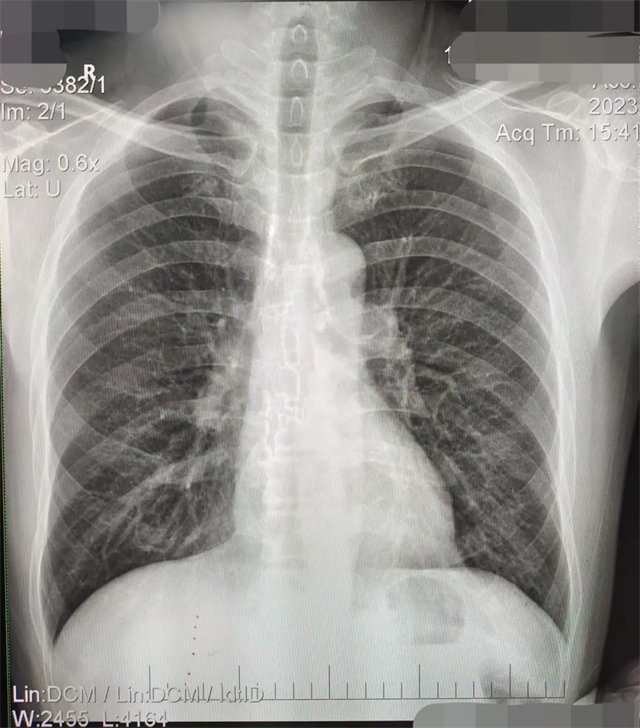

缺陷:雙側(cè)胸鎖關(guān)節(jié)不對(duì)稱,且有手機(jī)顯影。

解決:去除手機(jī)后,使患者左側(cè)緊貼成像件曝光。